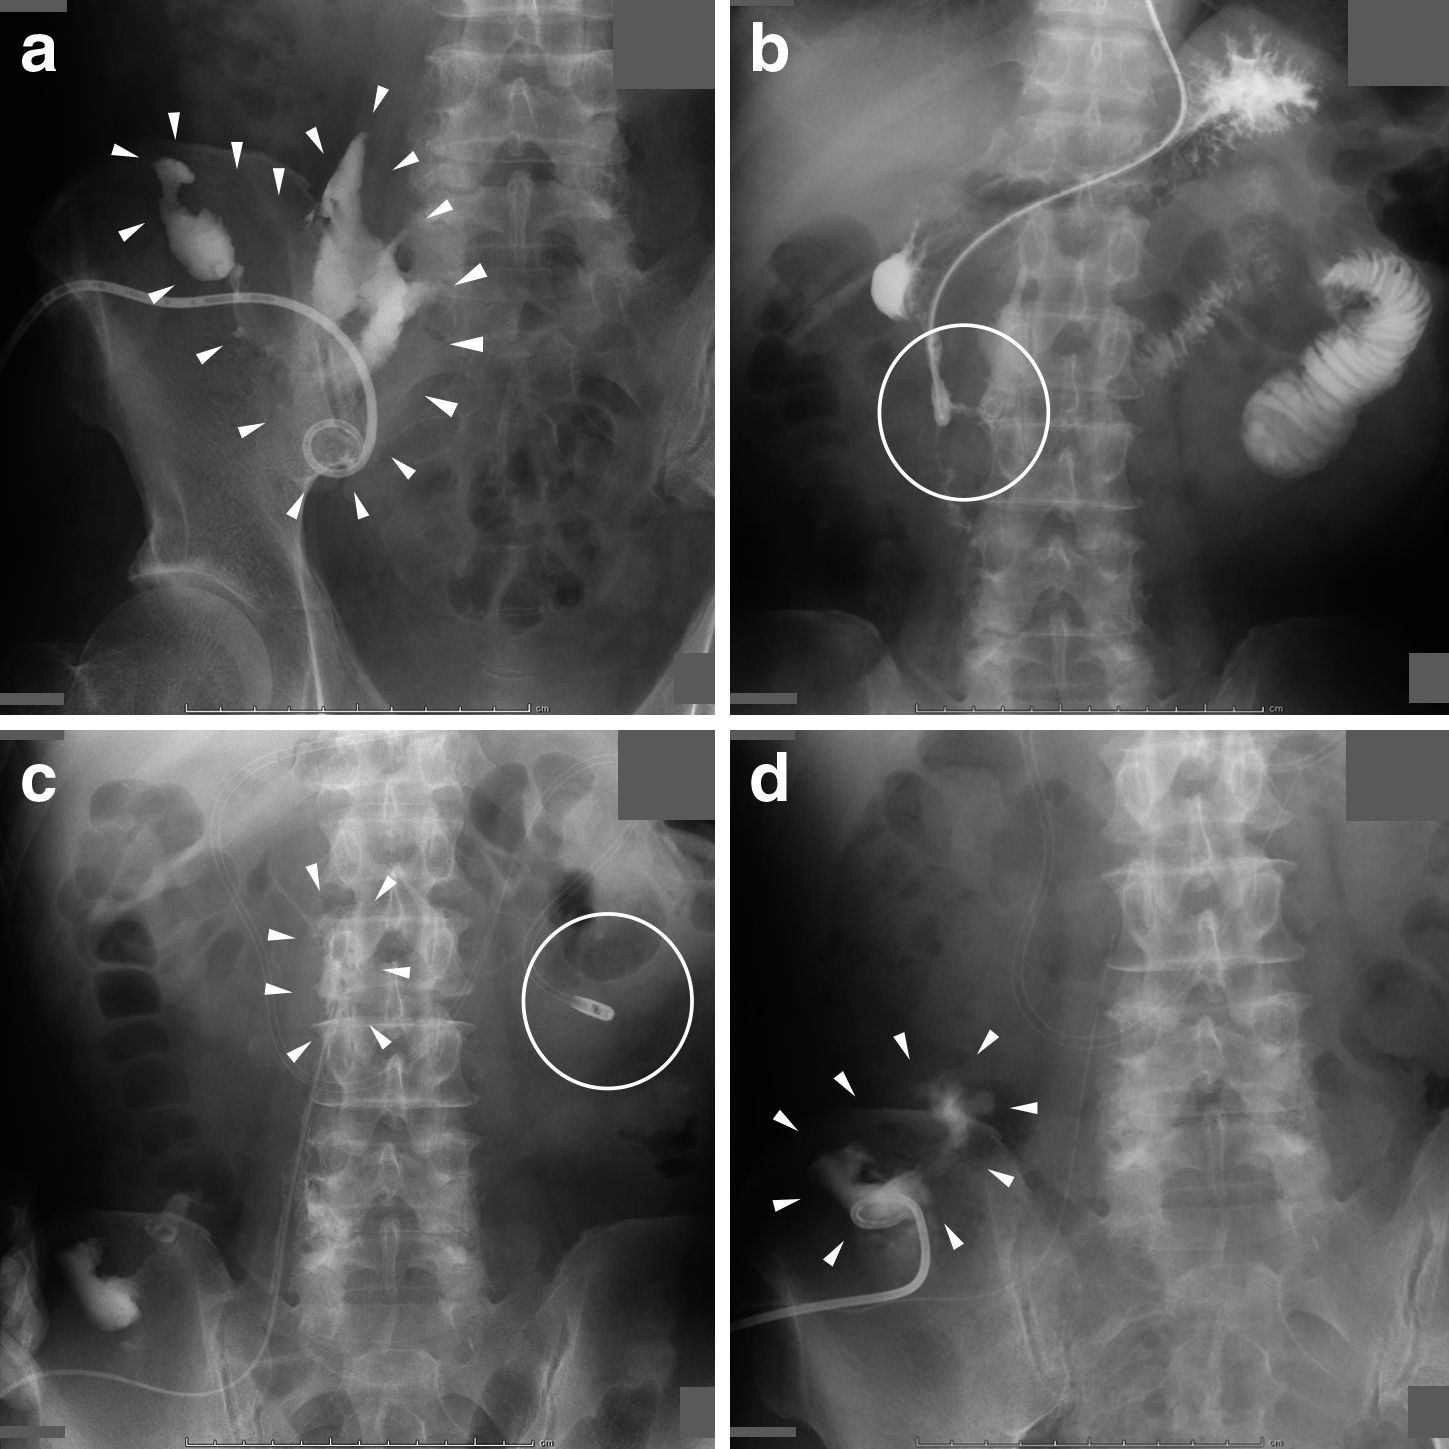

入院後経過:第2病日に透視下上部消化管内視鏡検査を施行したところ,明らかな憩室は存在せず十二指腸下行脚背側に穿通部位を認め,管腔内に膿汁排出を伴っていた(Fig. 1c).以上のことから,十二指腸潰瘍穿通に伴う後腹膜膿瘍と診断した.バイタルサインが安定していたことから,経皮的ドレナージ,絶飲食,抗菌薬(ピペラシリン・タゾバクタム)投与,PPI投与による保存的加療の方針とした.第3病日に,CTガイド下ドレナージを施行した.穿刺ルートの安全性を考慮し,まずは右骨盤内の膿瘍腔にピッグテールカテーテルを留置した(Fig. 2a).ドレナージは良好であり,黄白色の膿汁の排液を認めた.細菌培養検査はAerobic Gram-positive bacillus,α-hemolytic Streptococcusであった.ドレナージおよび抗菌薬投与に反応して炎症反応は速やかに改善を認め,第10病日には白血球数8,400/μl,CRP 1.19 mg/dlまで改善を得た(Fig. 3).第13病日に,穿孔部の評価を目的として,十二指腸下行脚に挿入したelemental diet(以下,EDと略記)チューブより造影を行うと,造影剤の腸管外への漏出を認めた(Fig. 2b).経腸栄養目的にEDチューブ先端を穿孔部以遠の空腸内に留置し,同日より経腸栄養を開始した.また,透視下に骨盤内の膿瘍腔からガイドワイヤーを先進させることで,穿通部位と連続する十二指腸背側の膿瘍腔内に内瘻化チューブを留置しえた(Fig. 2c).第21病日に施行した上部消化管造影検査により,穿通部の閉鎖を確認できたため同日より経口摂取を開始した.第28病日のドレーン造影では,十二指腸背側の膿瘍腔はほぼ消失しており,膿瘍腔は盲腸背側に残存するのみであった(Fig. 2d).盲腸背側の膿瘍腔に対しては,ピッグテールカテーテルの追加により膿瘍が消失したため,第42病日にはドレーンを全て抜去し,第45病日に軽快退院となった.

Fluorogram. a: A pig tail catheter was inserted into the right pelvic abscess cavity (white arrowheads). b: Leakage of the contrast medium injected through the ED tube (white circle). c: A drainage tube was placed in the abscess cavity behind the duodenum and directly connected to the perforation site (white arrowheads), and an ED tube was placed at the jejunum (white circle). d: The abscess cavity behind the duodenum disappeared and the cavity barely remained behind the cecum (white arrowheads).